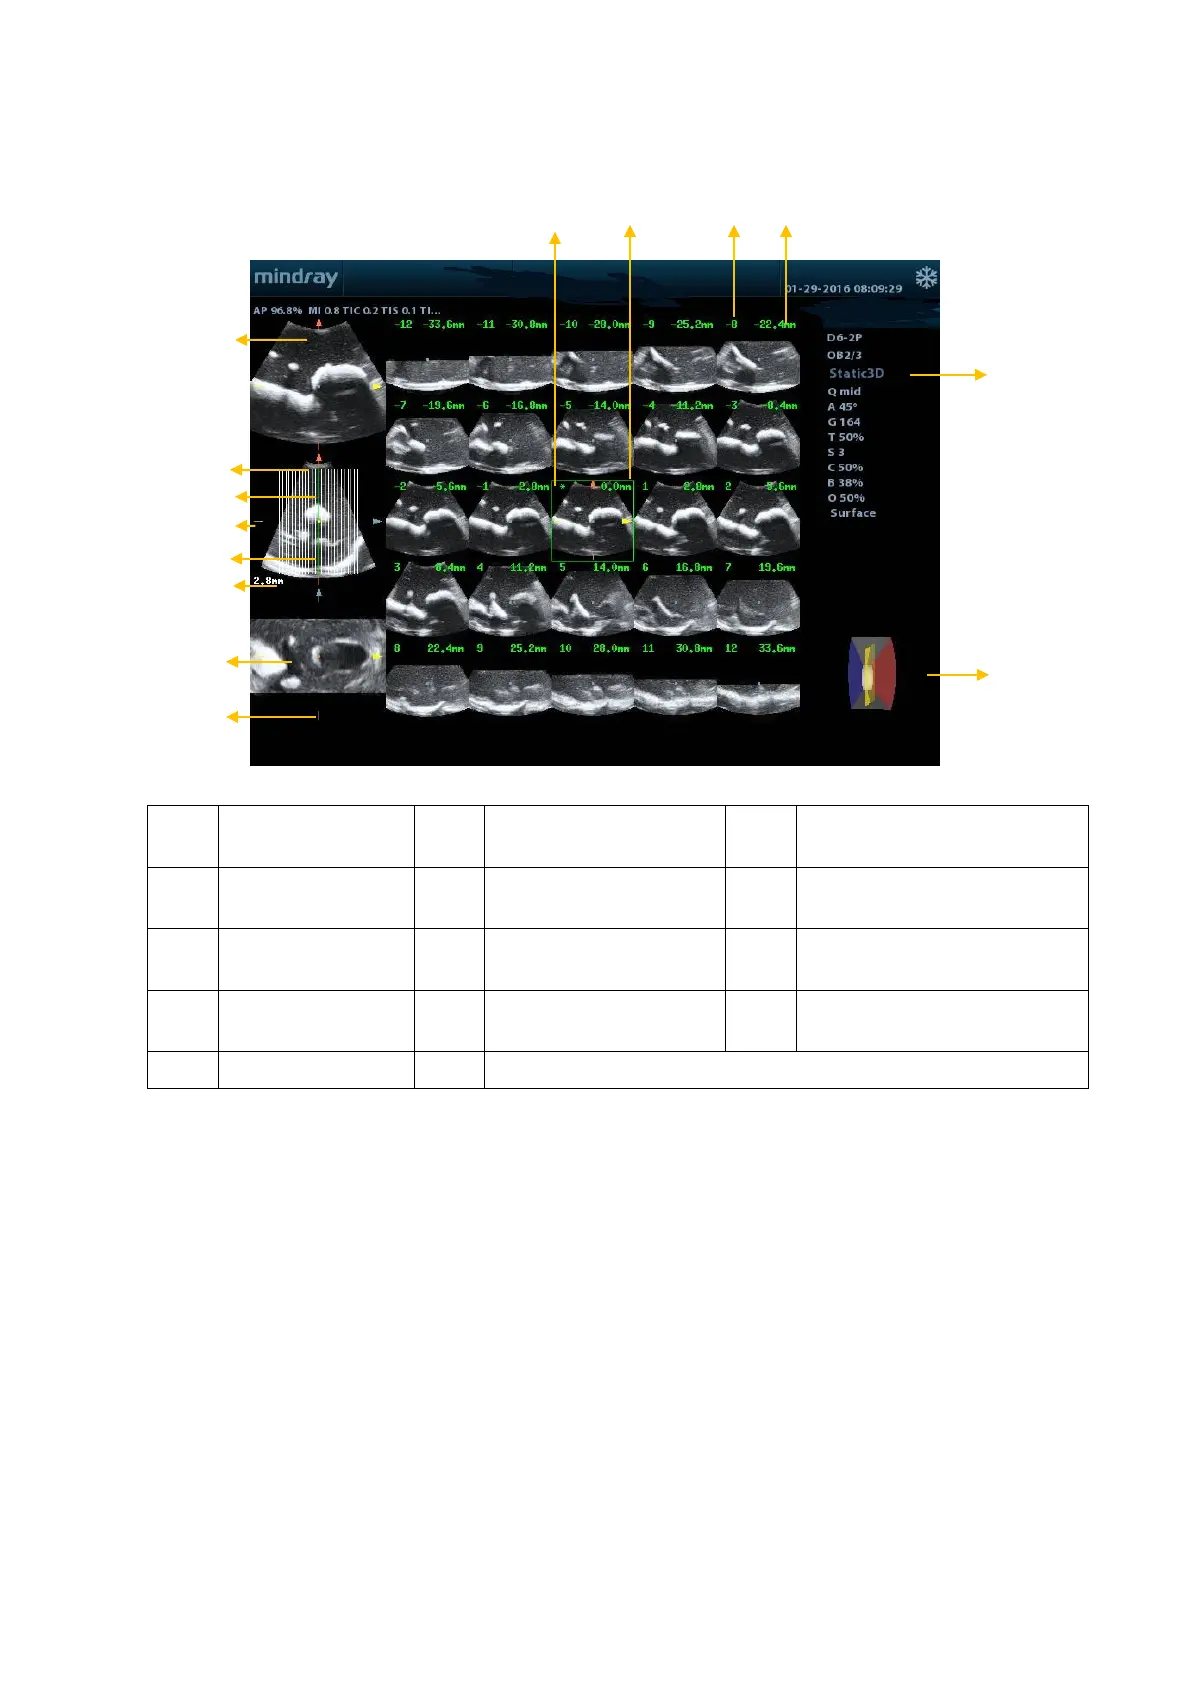

5.13.7.2 iPage Basic Functions and Operations

<1> A plane <2> B plane (the current

reference image)

<3> C plane

<4>

Y-axis

<5>

X-axis

<6>

Central section line (Current

active section line)

<7> Section line <8>

Space between two

planes

<9> Image parameter

<10>

Wire cage

<11>

Section plane order

number

<12>

Section plane position (to the

central plane)

<13> Central plane mark <14> Green box on the active image